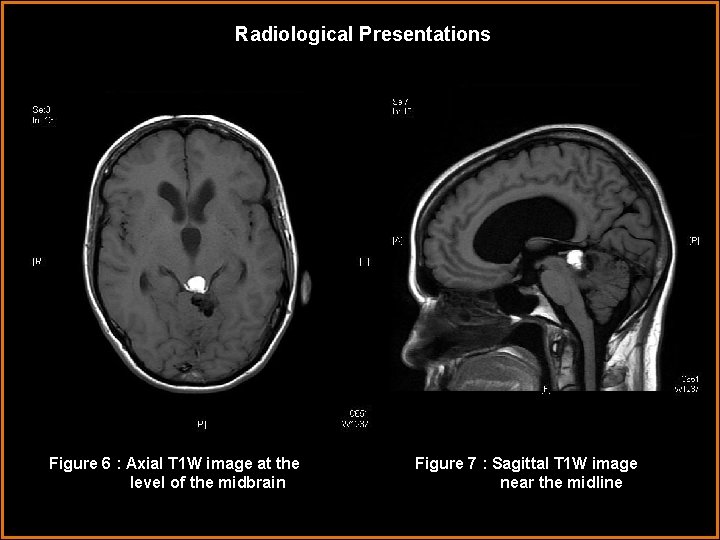

Radiological Presentations Figure 6 : Axial T 1 W image at the level of the midbrain Figure 7 : Sagittal T 1 W image near the midline

Findings and Differentials Findings: - An irregular, 3 cm mass is just posterior to the midbrain tectum and clearly below the internal cerebral veins on the sagittal MRI image placing it in the pineal region and quadrigeminal cistern. The anterior portion of the lesion is low in density on CT scan and demonstrates hyperintense T 1 W signal on MRI consistent with fat. The posterior portion of the lesion is ossified, as seen on figure 5 (the bone windowed CT image), and extends over the left superior cerebellar hemisphere. There is mild contrast enhancement on the post contrast T 1 W MRI image especially around the periphery of the ossified component. -There is mild vasogenic edema in the left cerebellum surrounding the mass. The mass also compresses the cerebral aqueduct leading to hydrocephalus with enlargement of the lateral and third ventricles.